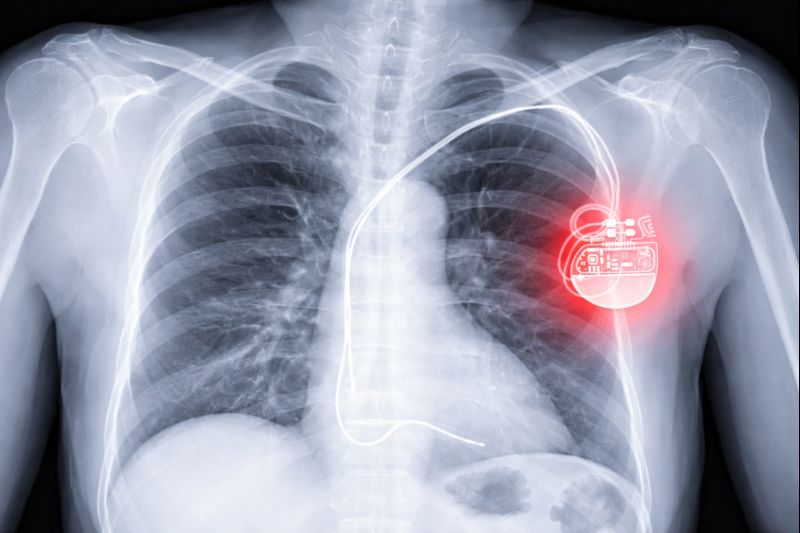

Herzschrittmacher und ICDs: besondere Vorsicht bei MRT Untersuchungen

Besondere Aufmerksamkeit erfordern Herzschrittmacher und implantierbare Kardioverter-Defibrillatoren (ICDs). Diese Geräte können auf starke Magnetfelder reagieren und müssen vor allem bei MRT-Untersuchungen sorgfältig berücksichtigt werden.

Wichtig: Geben Sie vor jeder Untersuchung alle Implantate an, insbesondere Herzschrittmacher oder ICDs, und bringen Sie Ihren Implantatspass mit.